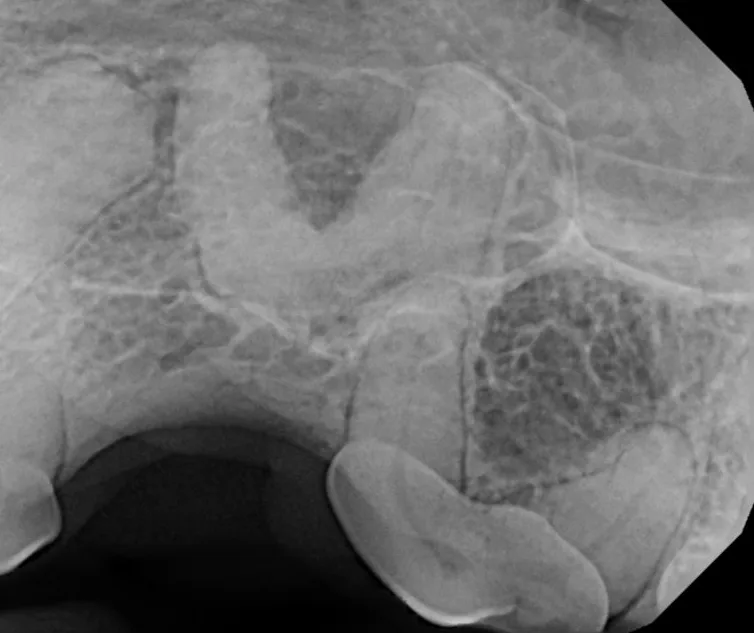

The Center now provides advanced imaging via cone beam CT. Cone beam CT is excellent for visualization of bony structures of the skull, nasal cavity, teeth, and ears. Cone beam CT is especially helpful for diagnosing dental disease and evaluation of jaw fractures. It can also be useful for evaluating the sinuses and tympanic bulla. Cone beam CT can be used in conjunction with nasal biopsy and culture to evaluate nasal discharge whether chronic or acute.

Pets can be involved in trauma that can cause fractures to their head, teeth, and jaw bones. Correctly repairing these fractures is extremely important for your pet to have normal function of their mouth. If a jaw fracture is allowed to heal in an abnormal position, your pet may have great difficulty chewing and can be in significant pain. Many fractures can be successfully treated with minimally invasive oral procedures, but more complicated cases may require bone plating techniques. The Center offers cone beam CT imaging which provides extremely detailed images of the bones of the head and skull. Advanced imaging with CBCT facilitates selection of the best surgical technique to get your pet back to eating and comfort as soon as possible.